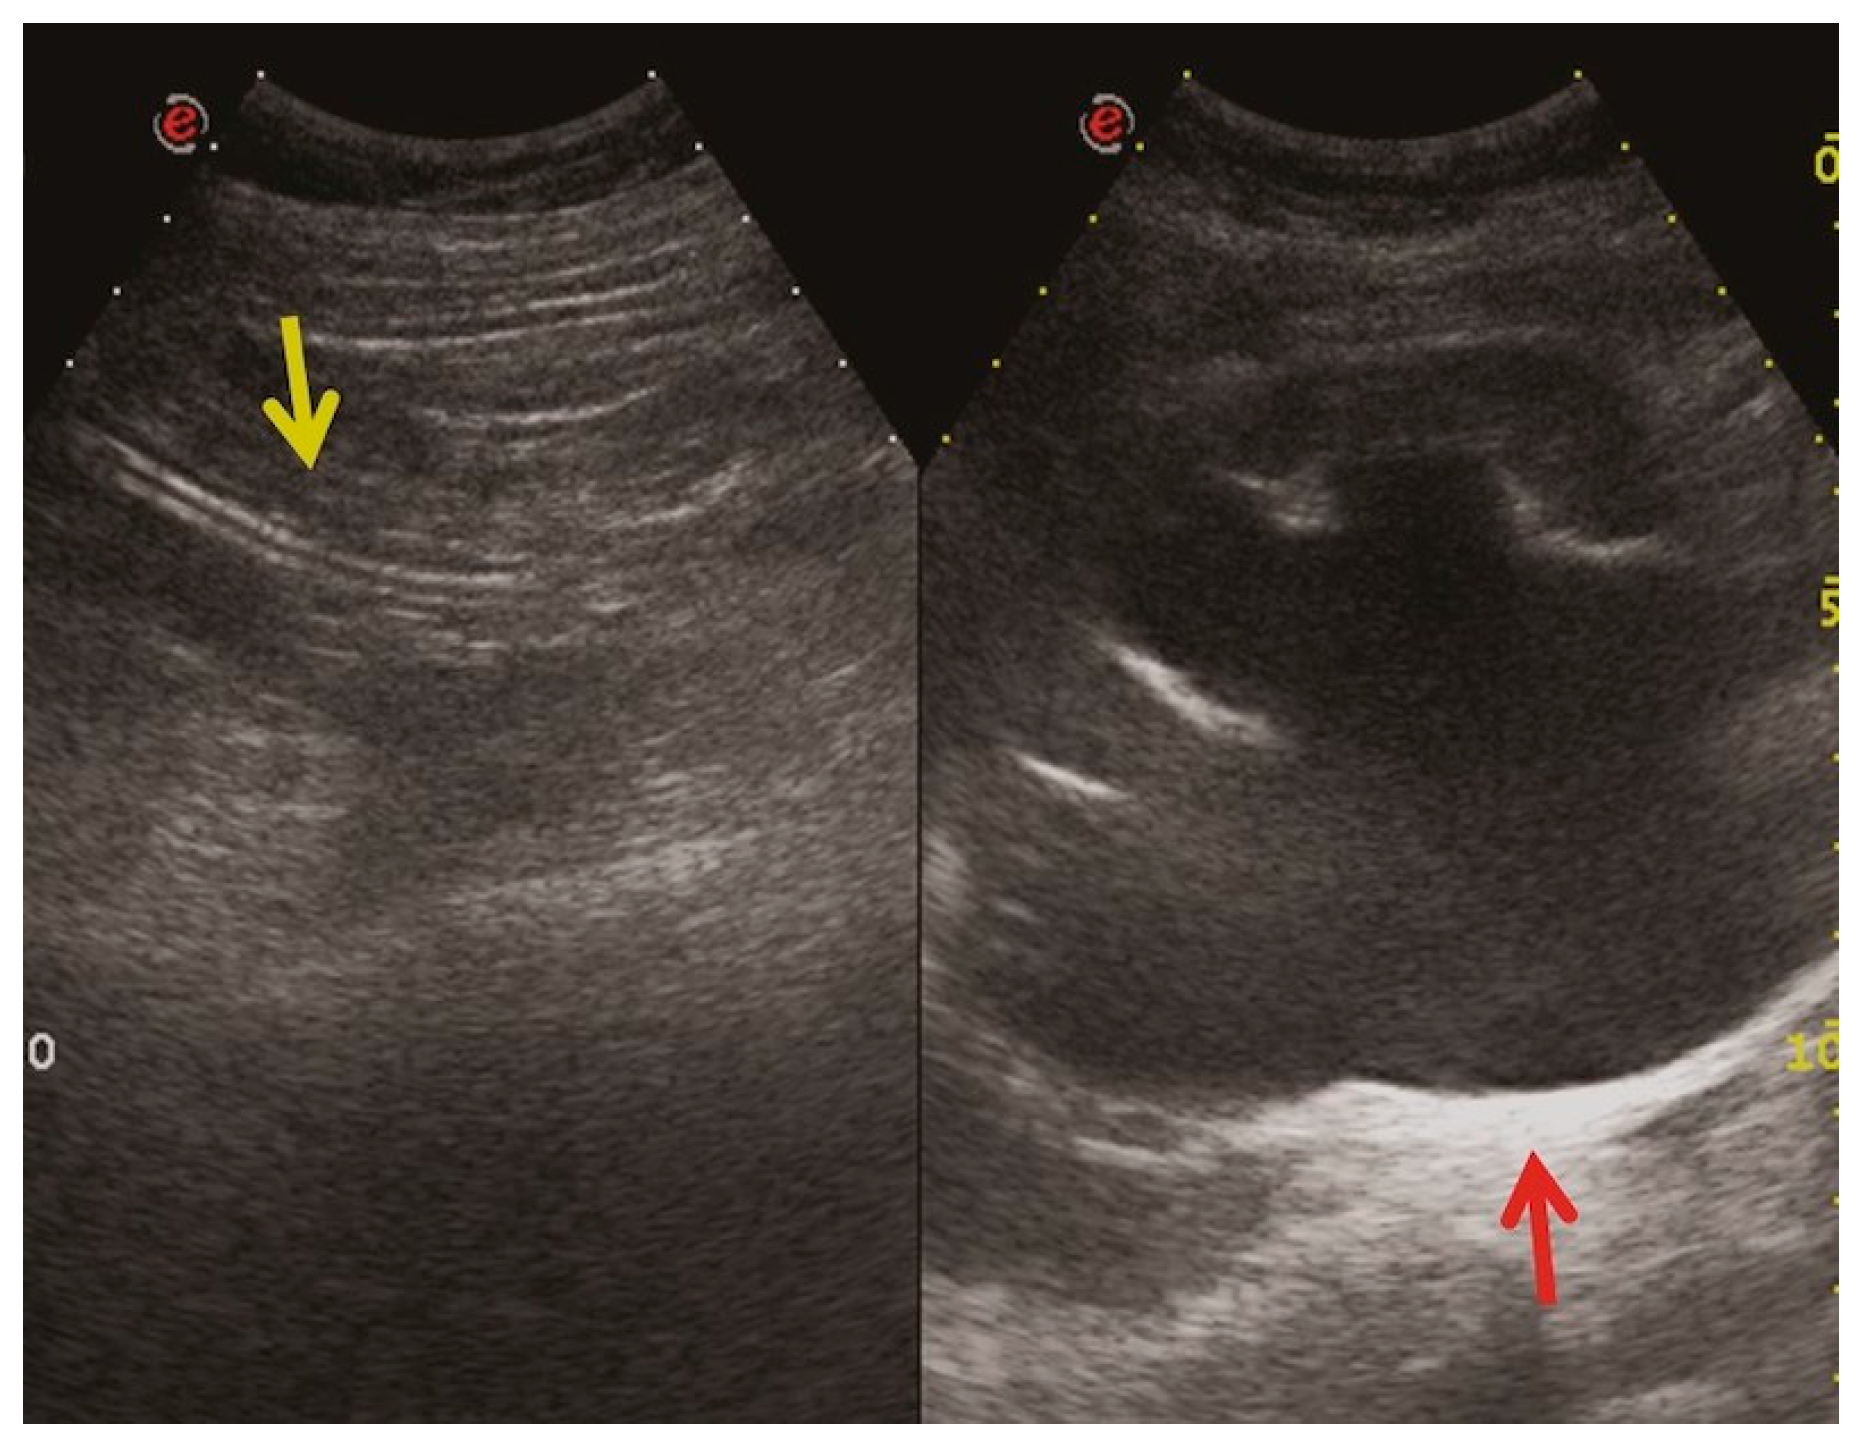

- Bleeding: The erosion of the stent into the arterial system is a rare and feared complication of ureteral stent placement, which can cause hematomas (Figure 10 and Figure 11), active bleeding, or pseudoaneurysm (Figure 12, Figure 13 and Figure 14). To avoid mortality from these complications, a high level of clinical suspicion is essential. Intermittent hematuria in a patient with a stent is typically the usual clinical scenario. However, massive hematuria and circulatory collapse can occur due to the manipulation of the ureteral stent [2,39].